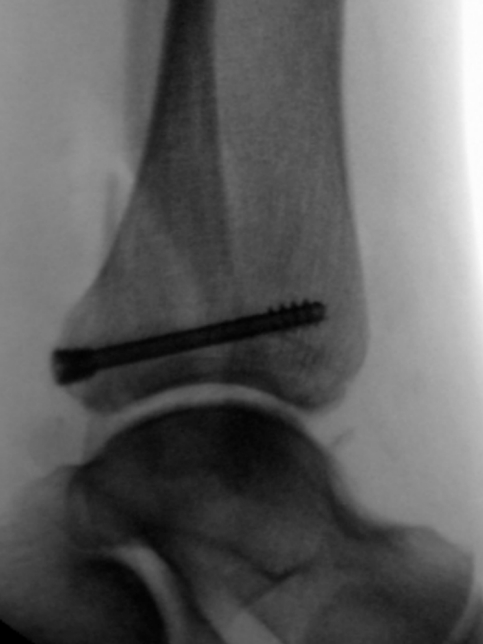

患者为83岁女性,于光滑平面滑倒后致三踝骨折,后踝为Bartonček 2型骨折,累及后外侧骨块及腓骨切迹(图2a–d)。相关合并症包括:骨量减少、软组织条件不良(皮肤呈羊皮纸样改变)、2型糖尿病(HbA1c 7.7%)。

image.png

(a)

(b)

(c)

(d)

图 2. (a–d):三踝骨折:(a) 前后位及 (b) 侧位X线片;(c) 轴位及 (d) 矢状位CT图像显示2型后踝骨折伴小中间骨块。